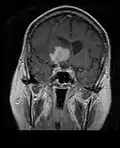

- Primary CNS Lymphoma

MRI T1 Axial

MRI T1 Axial MRI T1 Coronal

MRI T1 Coronal MRI T1 Sagittal

MRI T1 Sagittal MRI T2 Axial

MRI T2 Axial

- Restricted to brain, CSF, eyes, or rarely spinal cord

- Clinicopathologic variants include intracranial lesions, diffuse leptomeningeal or periventricular, vitreous, and spinal lesions.

- Intracranial primary CNS lymphoma are generally 75% supratentorial and 25% infratentorial.

- Primary CNS lymphoma is multifocal in 50% of AIDS-related variants, and multifocal in 25% of immunocompetent variants.

- MRI significantly underestimates extent of involvement; May appear focal on CT or MRI but parenchyma is typically diffusely involved.

- Intensely enhancing on MRI; may have a diffuse or “cotton wool” appearance on imaging.

- Classified as Stage IE NHL, because they are typically restricted to a single extranodal site